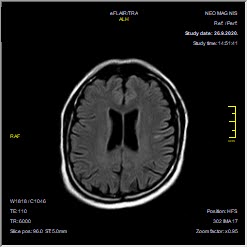

Foto: Privatna arhiva Foto: Privatna arhiva Foto: Privatna arhiva Radiolog pokazao snimak pluća i mozga 3 meseca posle kovida autor: Božica Luković Zdravlje 09. okt. 2020. 12:26 0 Podeli vest: Radiolog Aleksandar Ivković na svom blogu pruža naučni uvid u sve pojave koje je sa sobom donela pandemija koronavirusa. Rešio je da podeli kakvo je stanje jednog pacijenta tri meseca nakon što je preležao opaki virus. Podeli vest: Oglas Lekari i dalje ne znaju sa sigurnošću kakve sve posledice kovid 19 ostavlja po organizam. Postoje čak osobe koje više meseci pate od bolesti koju izaziva novi koronavirus, a mnogi prijavljuju i brojne tegobe koje ih muče i nakon negativnog testa.Niški radiolog, čije smo tekstove prenosili i ranije, ovog puta je odlučio da podeli snimke pluća i mozga svog pacijenta, koji je preležao virus pre tri meseca.Objavu sa bloga Aleksandra Ivkovića "Ljudi i ostale laži", prenosimo u celosti."Obećao sam da ću preneti kakvo je stanje pacijenata nakon kontrola. Ovde se radi o pacijentu koji je u grupi 50 - 60 godina, muškog pola, imao teži oblik kovida, nije bio na respiratoru, samo na kiseoniku.Prvi put kada sam ga pregledao bio je početak jula. Obostrana pneumonija. Foto: Aleksandar Ivković | Foto: Aleksandar Ivković Ime sam uklonio, datum se vidi, kao i ime ustanove. Ove bele fleke u plućima, koje kada se malo uveća, liče na mutno staklo, su ustvari žarišta pneumonije. Foto: Aleksandar Ivković | Foto: Aleksandar Ivković Kada bi ove bele "fleke" počele da se šire ka sredini, ka srcu, to bi značilo da se bolest širi i da se razvija citokinska oluja. Nije došlo do toga.Pacijent je došao na kontrolu nakon mesec dana. Žali se samo za zamaranje. Nema tegobe, samo želida vidi kakvo je stanje pluća. Foto: Aleksandar Ivković | Foto: Aleksandar Ivković Evidentno više nema onih zona zapaljenja. Bronhi su lako zapaljeni, mogu da se uoče mesta na kojima je bilo zapaljenje. Foto: Aleksandar Ivković | Foto: Aleksandar Ivković Ako se zagleda malo bolje prisutne su zone oštećenja alveola ali to ne spada u neki nalaz koji je zabrinjavajući.Skoro dva meseca kasnije, ponovo dolazi na pregled. Ovaj put nisu pluća u pitanju. Žali se da je konfuzan, da ne može da se seti nekih reči, da ne može da završi rečenice, da ima rupe u pamćenju.Urađen je MR pregled mozga. Foto: Aleksandar Ivković | Foto: Aleksandar Ivković Jedna ishemijska lezija, nekoliko mikroishemijskih lezija i atrofija mozga.Takav nalaz se uklapa u tegobe koje je pacijent opisao. Takođe se uklapa u ono što opisuju drugi da vide kod svojih pacijenata.Za one koji nisu shvatili još uvek - kovid 19 je opasna bolest. Od nje se umire, ostaju posledice. Nikako nije za igranje.Nikako nije ni za namerno zaražavanje, kako su neki pozivali", napisao je radiolog.***Bonus video:https://www.youtube.com/watch?v=PtivsKpglHYPratite nas i na društvenim mrežama:FacebookTwitterInstagram Srpski radiolog: 5 zabluda o asimptomatskim pacijentima Zdravlje 0 Ispovest srpskog radiologa: Golgota korone u sedam dana Zdravlje 0 Profesor Vujčić raskrinkao srpske teorije zavere o koroni Zdravlje 0 aleksandar ivković posledice koronavirusa Pratite nas na društvenim mrežama: Koje je tvoje mišljenje o ovoj temi? Učestvuj u diskusiji ili pročitaj komentare Budite prvi koji će ostaviti komentar Pošalji komentar Pročitaj komentare (0)